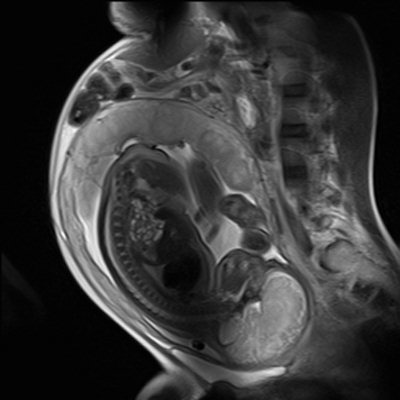

Acıbadem Kozyatağı Hastanesi Radyoloji Uzmanı Dr. Ümit Özcan: Fetal MR, gebelikte yapılan ultrasonografi incelemesinde annede ya da bebekte herhangi bir patolojik bulgu saptandığında, daha ileri ve ayrıntılı bir inceleme yapmak amacıyla kullanılmaktadır. MR incelemesi bebek için yapılabildiği gibi, gebelik döneminde anneye ait problemleri aydınlatmak için de güvenle kullanılabilir.

Uzm. Dr. Özcan: Bebeğe bağlı sebepler arasında Fetal MR’ın en sık kullanım alanı fetüsün santral sinir sistemi hastalıklarıdır. gebelik takibi sırasında bebekte saptanan beyin ya da omurga problemleri ultrasonografi ile sınırlı olarak değerlendirilebilir. Beynin ayrıntılı anatomik yapısı, beyin kıvrım ve katmanlarının gelişimi, omurganın gelişimsel bozuklukları Fetal MR ile ultrasonografiden daha üstün olarak gösterilmektedir. Ventrikülomegali adını verdiğimiz beynin boşluklarında genişleme, anne karnında gelişen beyin enfeksiyonları, kalıtımsal beyin hastalıkları, tümoral kitleler gibi patolojilerde Fetal MR görüntüleme ultrasonografiye ek bilgi sağladığı gibi klinik yaklaşımı da değiştirebilmektedir. İkiz gebeliklerdeki problemlerde, bebek beyninin kanlanması ve beyin parankiminde kanama gibi bazı sorunları tespit etmek konusunda Fetal MR ultrasonografinin gösteremediği değişiklikleri gösterebilir. Ultrasonografi’de bebeğin yatış pozisyonu ya da anne karnındaki su miktarı tanıyı olumsuz yönde etkileyebilir. Fetal MR’da bunlar problem oluşturmaz; bebek hangi pozisyonda olursa olsun, çok rahat görüntü alınabilir. Anne karnında ya da doğumdan hemen sonra cerrahi müdahale gereken fetuslarda MR planlama için kullanılabilir. Fetal MR sadece santral sinir sistemi hastalıkları için değil aynı zamanda fetüsün akciğer, karın boşluğu, kas-iskelet sistemi gibi yapılarını değerlendirmek için de kullanılmaktadır. Bebeklerin diyaframında bir problem olduğunda, örneğin karnındaki organların akciğere doğru yer değiştirmesi gibi durumlarda, akciğer kitlelerinde, akciğer hacim ve gelişimlerinin değerlendirilmesinde Fetal MR kullanılmaktadır. Bebeğin karnındaki yapıları değerlendirirken idrar yollarını, karaciğerini, safra kesesi gelişimini, kız bebeklerde yumurtalığa ait problemleri ya da oluşabilecek tümörleri yine Fetal MR’la ayırmak mümkün. Sadece bebeğe ait olan patolojileri değil, bebeğin eşi diye bilinen plasentaya ait patolojilerde de MR kullanabiliyoruz.

Ultrason ile Fetal MR arasındaki fark nedir?

Uzm. Dr. Özcan: Ultrason ses dalgası kullanarak görüntü elde eder, Fetal MR ise manyetik alanda görüntü elde eder. Fetal MR hiçbir şekilde radyasyon içermez. Eskiden anne ve fetus sağlığı için ultrasonografi kullanabiliyorduk ve çok gerektiği zamanlarda röntgen çekmek zorunda kalınıyordu. Anne adaylarının en çok korktuğu şey inceleme yapılırken bebeğin radyasyon almasıdır ancak Fetal MR’da incelemesi hiçbir şekilde radyasyon içermez.